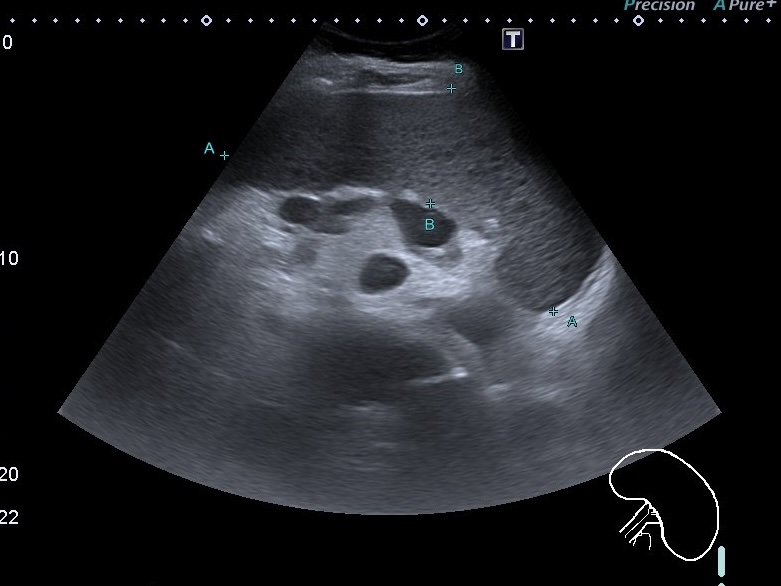

На скане представлены конгломераты характерных лимфопролиферативных лимфатических узлов возле верхней брыжеечной артерии и пятнистая гипоэхогенная селезёнка при лимфоме.

Обращает внимание на себя при гематологических заболеваниях изменения селезёнки. Селезёнка чаще увеличена, но может быть и обычных размеров. Капсула в основном не нарушена. Структура часто неоднородная, с гипоэхогенными очагами различных размеров. Эхогенность селезёнки часто снижена.